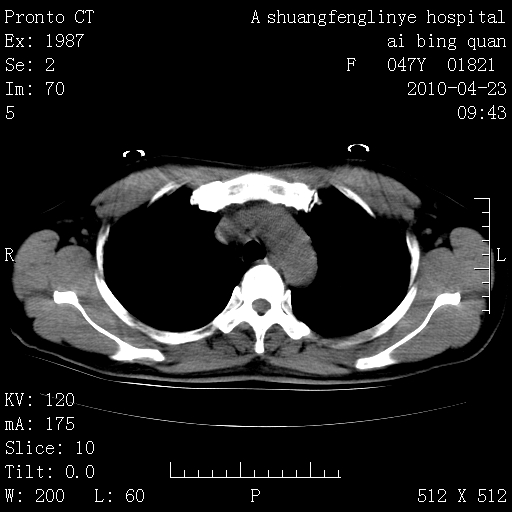

标题: CT25944:胸痛、气短、前几日高烧!肺Ca?请会诊!

kaolv 周围型肺癌并同肺转移

双肺多发结节,考虑转移瘤,肺癌肺转移不除外

周围型肺癌并肺转移

双肺多发结节,部分密度较高,最大结节边缘光滑。临床有“胸痛、气短、前几日高烧”病史。首选考虑:右肺感染性病变!建议积极消炎后复查!